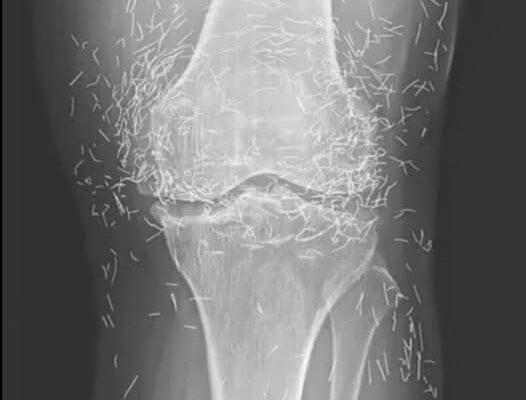

Years later, when doctors took X-rays to evaluate her knee condition, they weren’t prepared for what appeared on the images. Her knees were filled with dozens of bright, metallic flecks — tiny needles embedded deep within the joint area.

The findings were later documented in a case published by the New England Journal of Medicine.

Beyond inflammation, the needles created another problem: imaging complications. Metal objects can obscure parts of the anatomy on X-rays, making it harder for doctors to clearly assess joint damage or disease progression.

Even more concerning, the presence of metal inside the body can make certain scans dangerous. MRI machines rely on powerful magnetic fields, and embedded needles may shift during scanning, potentially damaging blood vessels or surrounding tissue. In short, future diagnostic options for this patient became limited.